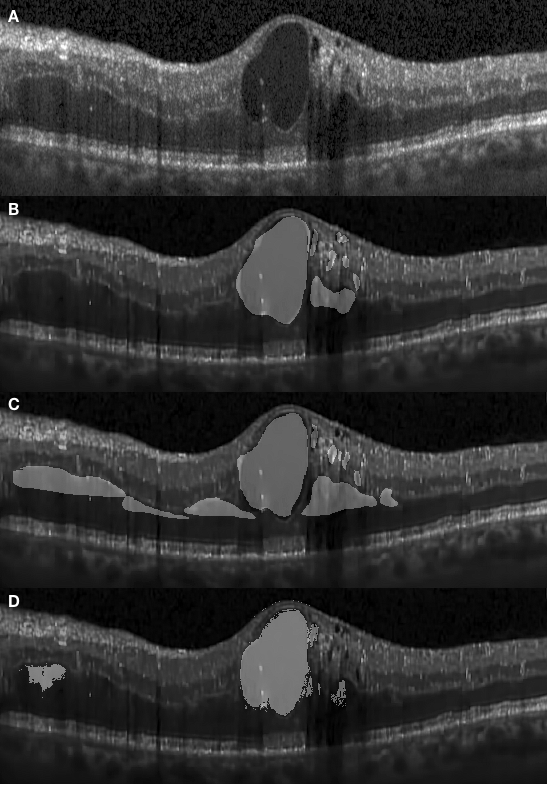

The appearance of fluid edema in OCT images is often shown with a higher contrast against surrounding tissue. Figure 4.1 (A) depicts the foveal region affected with a fluid edema. The dominant edema detaches retinal layers and small edema regions surround it sporadically. It can be seen on the framework results that the boundaries of the dominant edema are accurately segmented out, and the smaller edema on the right-hand side is also segmented individually with clear boundaries. Although two graders annotated the same fluid regions, the framework shows an improvement in terms of boundary recall. A significant inconsistency among manual segmentations on the left side of the fovea has also been observed. Because our network was trained using labels previously provided by the first grader, it is prone to be more similar to their results.

In Fig. 4.3 (D) we demonstrate results of our framework operating on images depicting more severe morphological conditions. The retinal layer in Fig. 4.3 (A) was destroyed by a large section of edema which mixed various shapes of fluid and concrete edemas. The central fluid section is fused with the concrete part on both the left and the right-hand side of the images, where both sections were successfully segmented by our approach. It can be seen that our approach shows that the segmentation achieved is consistent with the appearance of the pathology and accurately covers the entire region. Several small sections were also well segmented but some slimmer region is not detected since it is too slim to be perceived by the network. In Fig. 4.5, we present additional results from severe conditions that present complex structure appearances.

Apart from the segmentation of large areas, there are still some cases where our approach failed to segment the target region accurately. One such event occurred when small target regions were not segmented out, as shown in Fig. 4.1 (D). In this case, the small regions were affected by speckle noise and smoothing effects caused by the pre-processing resulting in the small regions being undetectable by the framework, due to their small initial size leading to them being smoothed out after several pooling layers. In another case, some target regions were only partially segmented, as shown in Fig. 4.4.